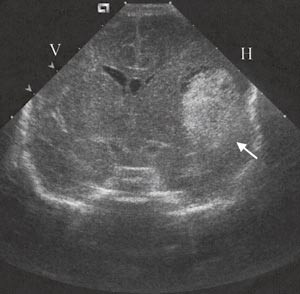

I uke 27 ble det påvist en intracerebral blødning som målte 1 x 1 cm basalt i venstre temporoparietalregion. Siden det var risiko for nye blødninger, ble det besluttet å forberede forløsning ved å gi steroider for lungemodning. Etter 48 timer ble det gjort elektiv sectio, med forlikelige trombocytter (HPA-1bb) i beredskap.

Ultralydundersøkelse av hodet etter fødsel bekreftet en blødning i temporoparietalregionen (fig 3).